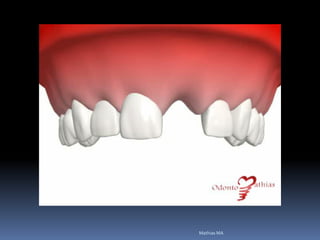

Atrofias óssea

Redução das dimensões ósseas ideais

•Estabilidade implantar

•Estética

•Função

Atrofias ósseas

•Procedimentos de enxertia óssea para

restabelecimento de dimensões perdidas

•Compensações dos tecidos perdidos nas

próteses